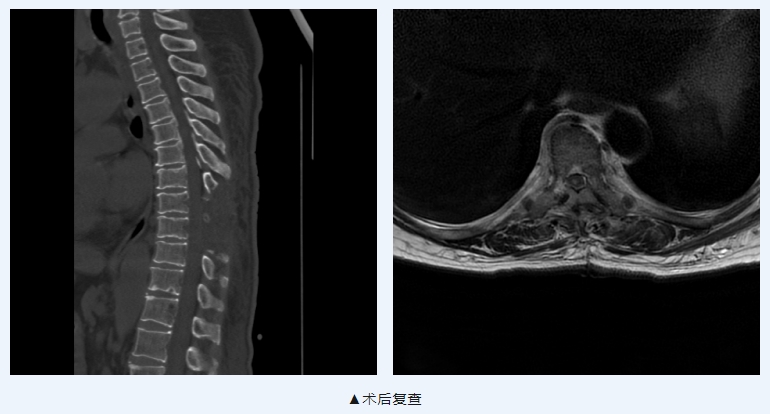

患者今年70岁,因“双下肢麻木伴感觉功能减退1年余”入院。入院查体发现:右下肢腹股沟以下浅感觉减退,左下肢踝关节以下浅感觉减退;行胸椎增强MRI提示:T9椎体水平椎管内占位,性质待定,考虑髓外硬膜下肿瘤性病变-脊膜瘤可能。

我院脑科中心四区在排除相关手术禁忌后,在我院博士工作站专家、南方医科大学珠江医院神经外科神经创伤与神经重症医学科主任王清华教授的指导下为患者成功施行了“显微镜下胸9椎管内肿瘤切除术+硬脊膜修补术”。术后予营养神经、减轻水肿等对症治疗,患者双下肢麻木及感觉障碍症状明显好转,无腰痛、肢体乏力等并发症。